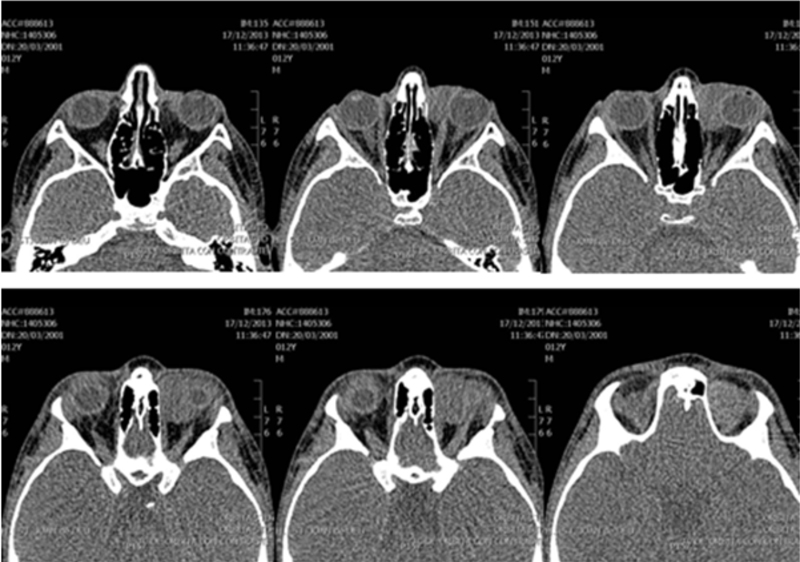

La tomografía computerizada (TC) de órbita (

Figura 1 y

Figura 2) evidenciaba una lesión ocupante de espacio de densidad de partes blandas de 3 centímetros de diámetro localizada a nivel superomedial de la órbita izquierda y que desplazaba el globo ocular anterolateralmente, así como al recto interno y el recto-oblicuo superior. No se apreciaban lesiones óseas, ni afectación de senos paranasales ni frontales.

Figura 1. TC órbita (axial).